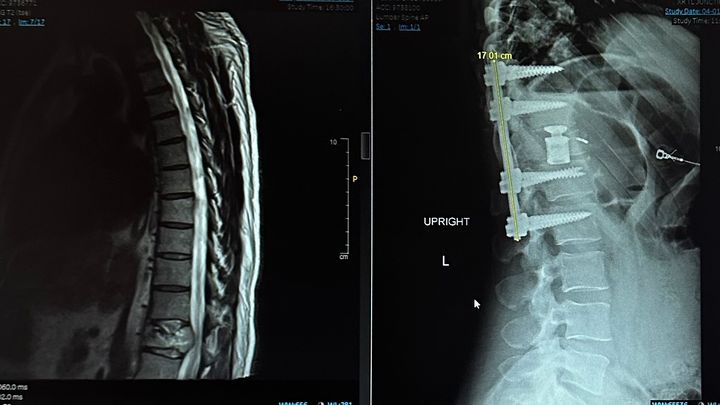

Jay has been battling back pain for quite some time now and went in to the Whitefish ER on Friday, March 29. They did a CT scan to find a tumor degrading the vertebrae and pinching his spinal cord which destabilized the structure of his spine. They life flighted him out to Billings for an emergency surgery. This 16 hour surgery was intense but successful in removing the tumor from the spinal cord area and stabilizing the vertebrae.

During this, the scans have shown Jay has cancer in his spine, pelvis, kidneys, lungs and ribs.